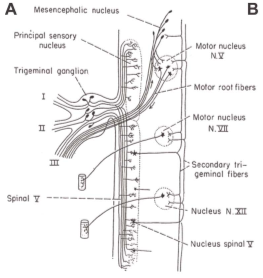

VPT is a modification of various other tractotomy procedures, including that of the descending tract of the trigeminal nerve, first introduced by Sjöqvist in 1938 (7-13), largely abandoned due to complications, including lower cranial nerve dysfunction, proprioceptive issues and dysesthesias. The technique employed by the VPT targets the fibers of the spinal trigeminal tract (SpTV) before they coalesce into a compact tract (Figure 3). In this initial portion, the fibers of the SpTV form a lenticular shaped elbow after they separate from the intrapontine portion of the trigeminal nerve. This elbow is just ventrolateral to the principal sensory and motor trigeminal nuclei. By using this as a target, the tractotomy mechanically disrupts the temperature and pain fibers from the face and stops short of the spinal nucleus or motor nucleus of the trigeminal nerve. The VPT also disrupts fibers cephalad to where the sensory fibers of VII, IX or X join the SpTV, therefore avoiding damage to those fibers. This method was devised in order to minimize the risk of other complications, such as anesthesia dolorosa or neurotrophic keratitis that can occur after more generalized damage to the trigeminal nerve after rhizotomy or radiofrequency ablation.